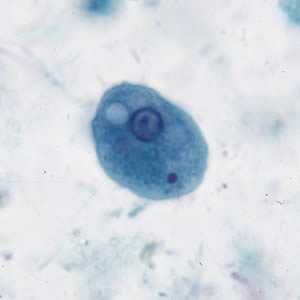

I. buetschlii cysts stained with trichrome.

Figure A: Cyst of I. buetschlii stained with trichrome. In this specimen, both the nucleus and large glycogen vacuole are visible.

Figure B: Cyst of I. buetschlii stained with trichrome. In this specimen, both the nucleus and large glycogen vacuole are visible.

Figure C: Cyst of I. buetschlii stained with trichrome. In this specimen, both the nucleus and large glycogen vacuole are visible (arrow).

Figure D: Cyst of I. buetschlii stained with trichrome. In this specimen, both the nucleus and large glycogen vacuole are visible.